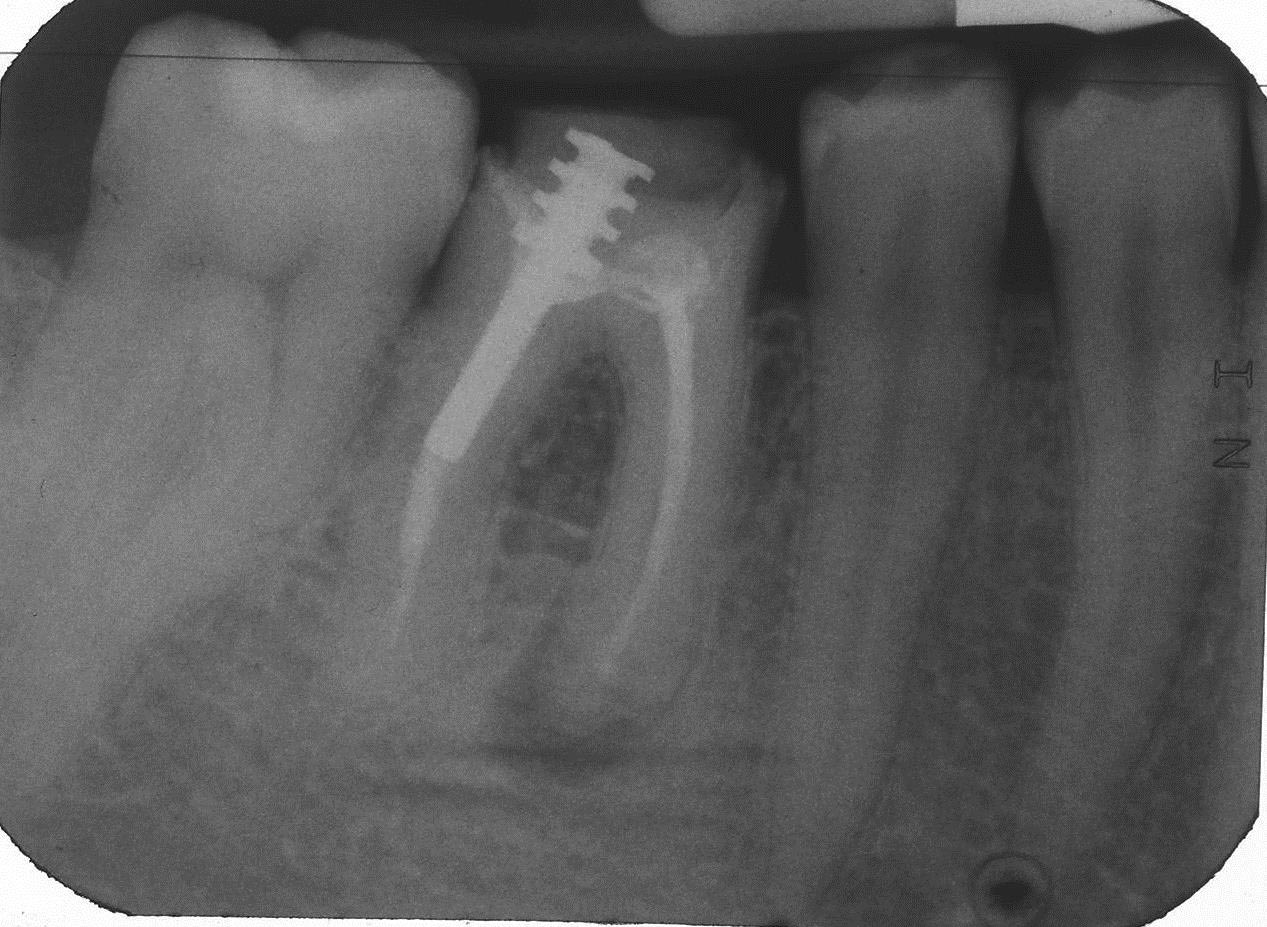

1 Pre-OP 12.09.2008 Veröffentlicht 6. Oktober 2013 am 1267 × 927 in Teilrevision Zahn 46 – Wie würden Sie entscheiden?